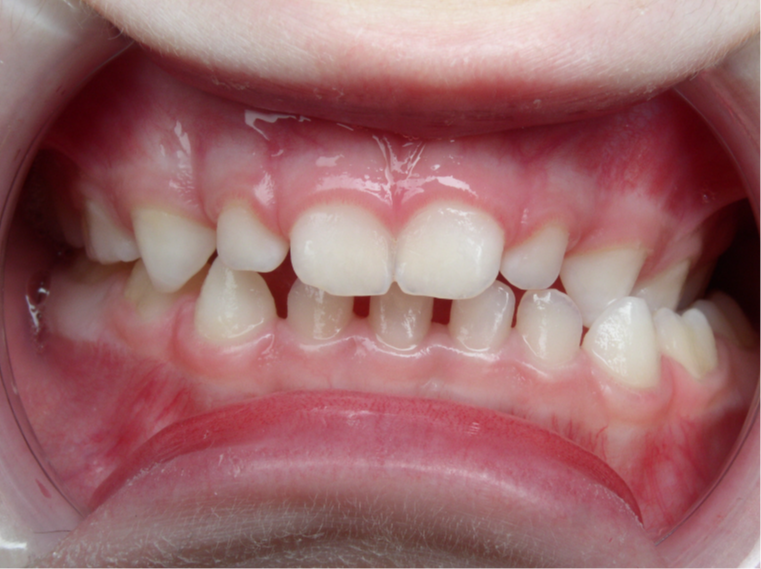

bilan début et fin de traitement